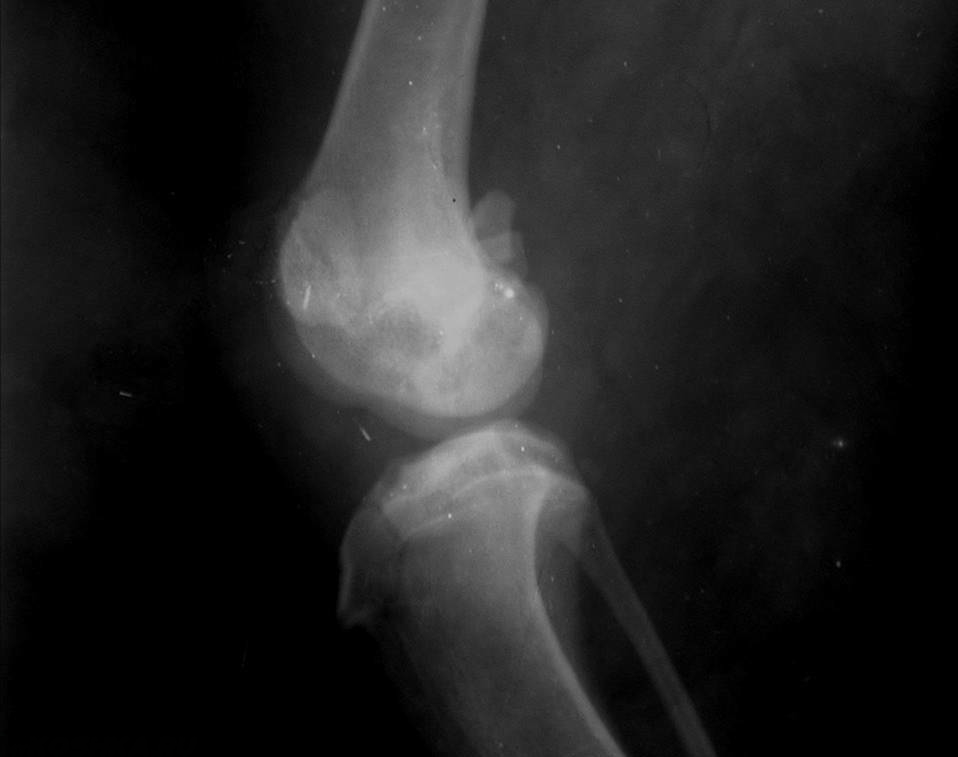

При таких симптомах, как хромота и увеличение кости в объеме, часто делают рентгеновские снимки пораженных костей, на которых можно увидеть развитие опухоли и иногда некоторые характерные изменения, например, литические изменения кости.

Для диагностики данного заболевания применяется рентгенографическое исследование.

Рентгенография является необходимым методом диагностики остеосарком у собак. Для идентификации малейших изменений на ранних стадиях развития костных опухолей нужна очень хорошая техника, поскольку увеличение необходимо при исследовании костных трабекул. Для съемки иногда может потребоваться седация, так как костные опухоли очень болезненны, что может вызывать затруднения при правильном позиционировании животного. При проведении рентгенографического обследования можно выявить следующие характерные признаки остеосарком у собак:

- Остеопластические и остеолитические проявления рака кости.

- Слабо выраженные края областей разрушения кости.

- Утончение и лизис кортикального слоя.

- Появление «треугольника Кодмана» и радиальные шипы в виде «солнечных лучей», так называемые «спикулы».

- Пятнистый склероз (повышение плотности кости).

- Длинные переходы зоны к нормальной кости, никаких перегородок.

- Отек мягких тканей и пр.